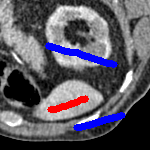

We now introduce two recent methods that incorporate user input to perform selective segmentation. Each involves input in the form of foreground/background regions to indicate relevant structures of interest. An example of this can be seen in Fig. 18, where red regions indicate foreground and blue regions indicate background. We compare against the work of Nguyen et al. Nguyen:12 , which uses a similar convex relaxation framework to the proposed approach, and Dong et al. SRW , which uses a variation of the random walk approach. We summarise the essential aspects of each approach in the following.

In order to further establish the robustness of our method, we now introduce the results of testing our approach against competing interactive segmentation methods on a larger data set. The results are presented in Fig. 17, showing a boxplot of accuracy in terms of TC on a set of 30 CT images (excluding outliers). The target structure we consider is the spleen, as this consists of a relatively homogeneous foreground, appropriate for the approach considered. The data has been manually contoured providing ground truth data for the image set. We compare CAC Nguyen:12 and SRW SRW against our method with five variations of user input for each image. It is worth emphasising here that the input used in the tests is identical for each approach and was not refined in any way. It was designed to mimic what a user, unfamiliar with each approach, might select intuitively. A representative example for three images is shown in Fig. 18. This shows foreground (red) and background (blue) user input regions. For our method, we define the red region as as discussed in §1 and enforce hard constraints on the blue region. We refer to the results of the proposed approach using this input as Ours (i). We also include results of randomising the user input in an identical way to §7.3. For each image we generate 1000 simulated user input choices, which we present as Ours (ii). It is important to note that the difference between Ours (i) and (ii) is only the definition of . The method and parameters are fixed between each.